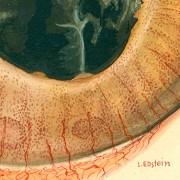

Lilly Ebstein Lowenstein (1897-1966) led a life between science and art, drawing and taking photographs in the fields of Medicine and Zoology. In her work, Lilly combined her technical knowledge of photography and drawing, the study of the sciences and a remarkable talent for aesthetics. She was born in Germany and studied at the Lette-Verein School in Berlin from 1911 to 1914. In 1925, she immigrated with her husband and two children to São Paulo. In 1926, she became an illustrator and photomicrographer at the Illustration and Photography Department at the School of Medicine (USP, as of 1934), which she headed for thirty years after 1932. Lilly collaborated at Instituto Biológico de Defesa Agrícola e Animal (the Biological Institute for the Defense of Agriculture and Animals), from 1930 to 1935, namely in the Avian Pathology Department. A life with art dedicated to the research and dissemination of science.